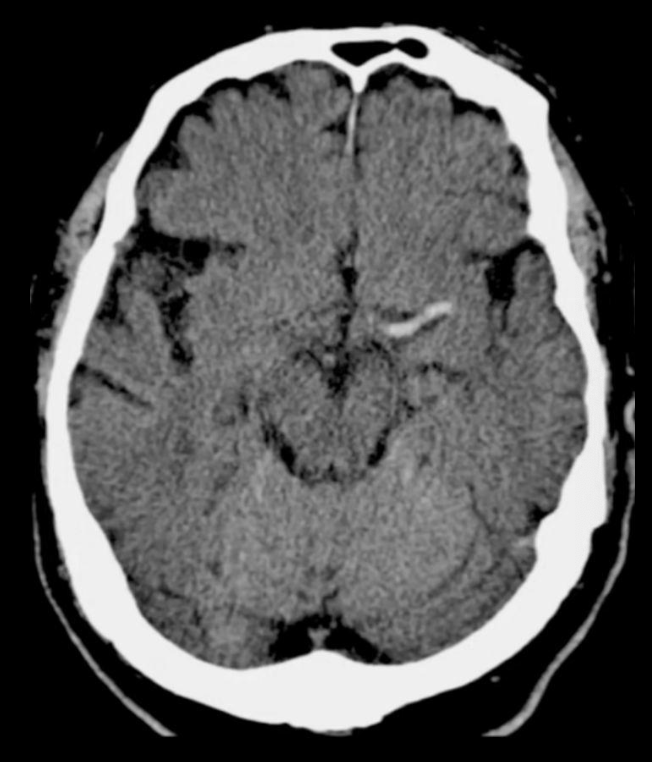

EVC isquémico

Fase hiperaguda